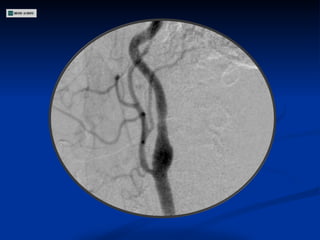

ECODOPPLER DE VASOS DEL CUELLO Estenosis 80-90 % en segmento inicial de Carótida Interna Derecha Estenosis 50-60 % en Carótida Interna Izquierda Carótidas externas permeables con flujos conservados Arterias Vertebrales permeables

Angiografía

ECODOPPLER DE VASOSDEL CUELLO Estenosis 80-90 % en segmento inicial de Carótida Interna Derecha Estenosis 50-60 % en Carótida Interna Izquierda Carótidas externas permeables con flujos conservados Arterias Vertebrales permeables